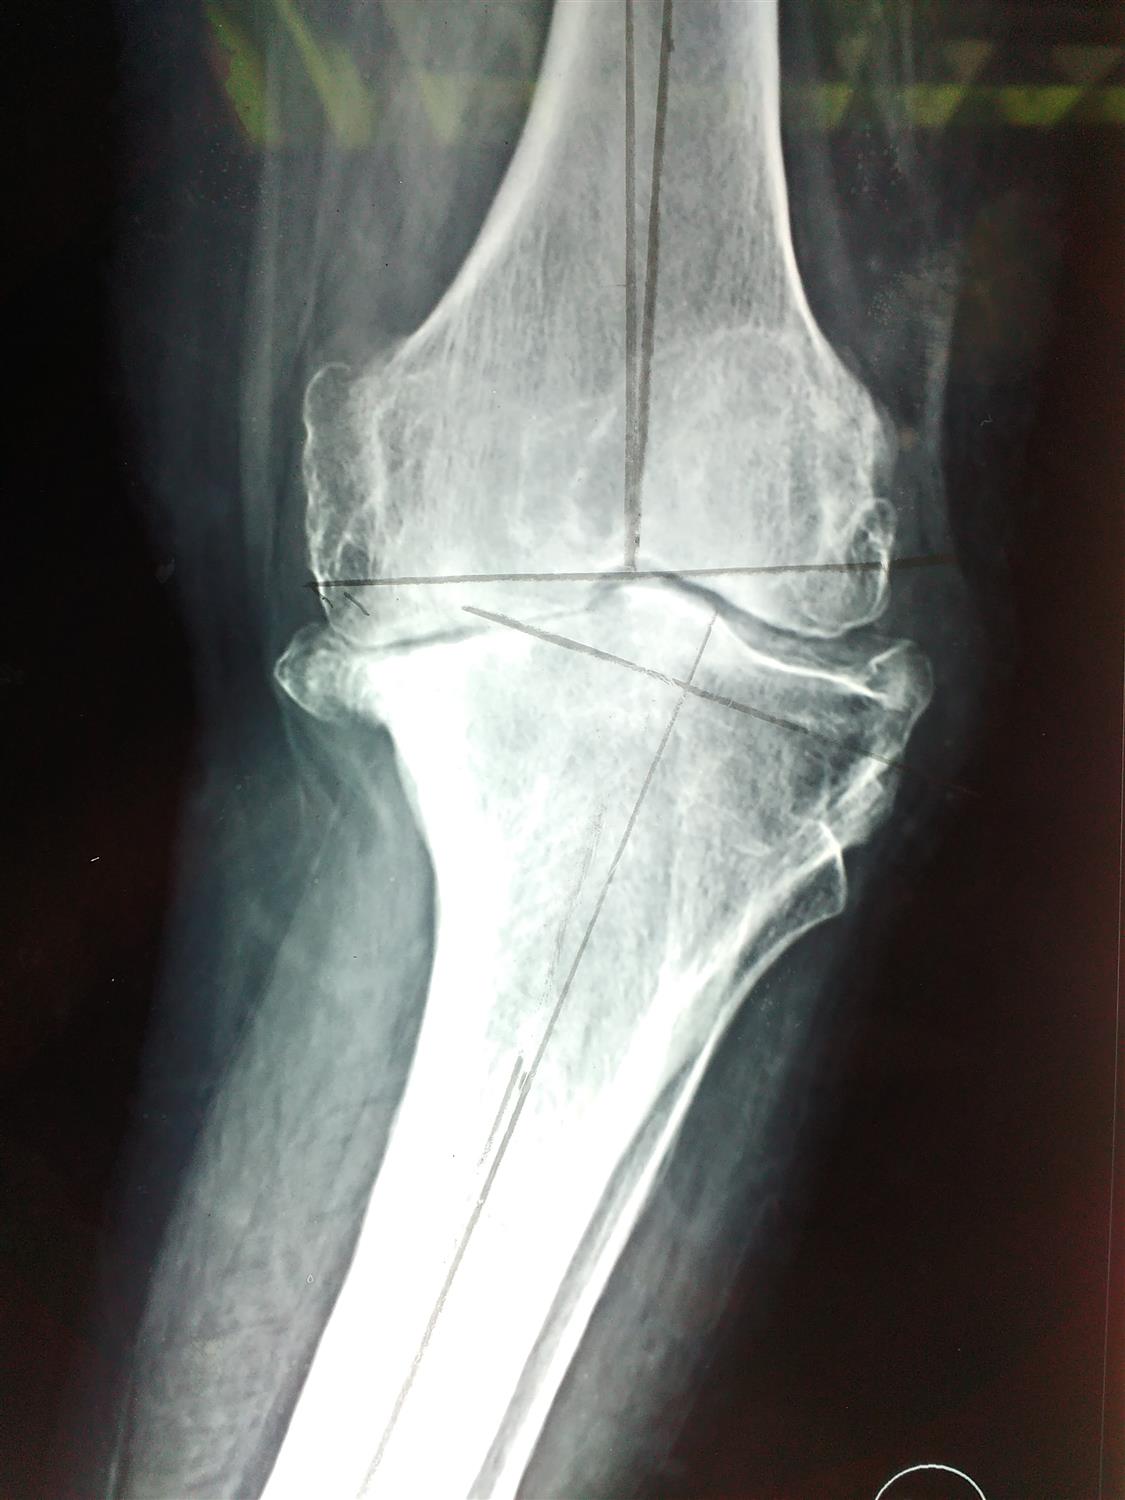

Knee Balancing Orthobullets . Measured resection is a total knee arthroplasty (tka) technique that relies on bony landmarks to set component placement and adapts the soft tissues to the chosen implant position. This article reviews different techniques to position tka implants, including kinematic alignment, which aims to restore the patient's. Soft tissue balancing during total knee arthroplasty (tka) is an important step for optimizing the outcome of the procedure and providing. Balance flexion and extension gaps by adjustment of polyethylene bearing thicknesss We compared knee arthroplasties performed using either a measured resection or gap balancing technique to determine if either operative.

Balance flexion and extension gaps by adjustment of polyethylene bearing thicknesss Soft tissue balancing during total knee arthroplasty (tka) is an important step for optimizing the outcome of the procedure and providing. This article reviews different techniques to position tka implants, including kinematic alignment, which aims to restore the patient's. We compared knee arthroplasties performed using either a measured resection or gap balancing technique to determine if either operative. Measured resection is a total knee arthroplasty (tka) technique that relies on bony landmarks to set component placement and adapts the soft tissues to the chosen implant position.